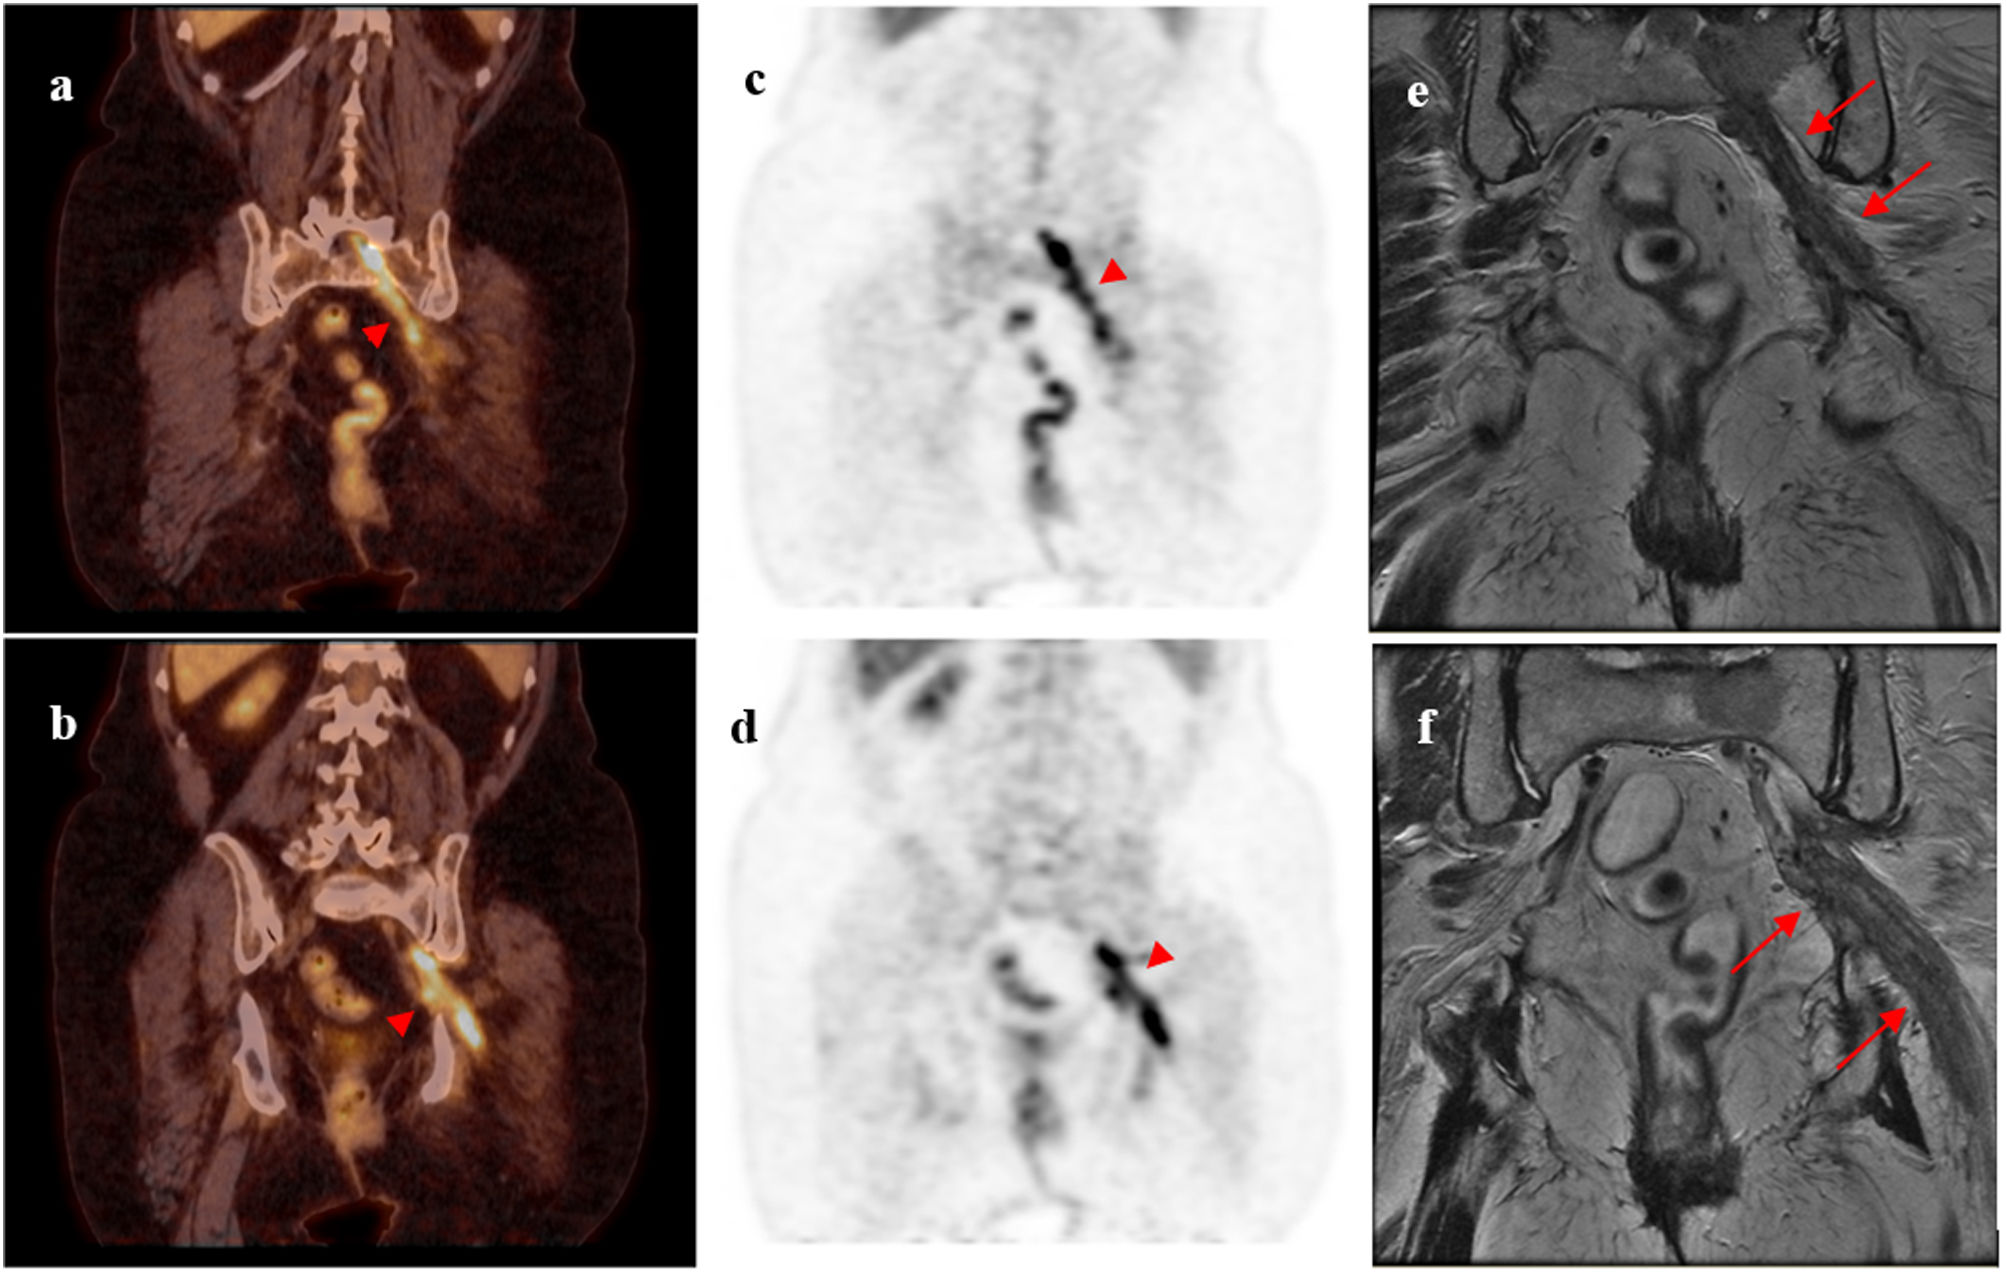

Revista Española de Medicina Nuclear e Imagen Molecular Infiltración tumoral del nervio ciático: hallazgos en 18F-FDG PET/TC

Infiltración tumoral del nervio ciático: hallazgos en 18F-FDG PET/TC

Sciatic nerve tumoral infiltration: 18F-FDG PET/CT findings